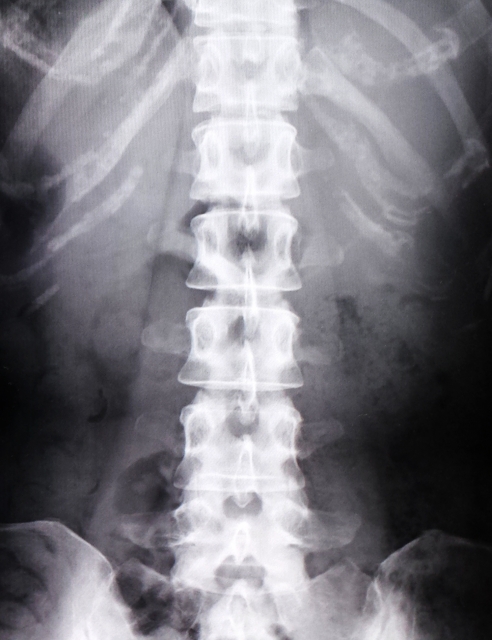

例えば腰椎椎間板ヘルニアだと、腰椎の椎間板が飛び出て神経を圧迫して足のしびれなどの症状を起こします。

他にも神経を圧迫するものには腰部脊柱管狭窄症もあります。骨が変形したり靭帯が太くなることで神経を圧迫します。